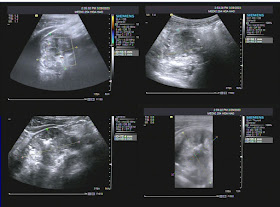

Chest X-Rays noted a blurred node close by the clavicle which could not differentiate from anterior mediastinal tumor or lung tumor. Vascular ultrasound could detect a yin-yang sign of a round mass with thrombus of the wall and MSCT could determine exactly the size, location, and reconstruct in 3D view.

Male patient 34 year-old for check-up. A 69 round mass was on the left clavicle. Yin-yang sign positive and thickening wall due to thrombus on ultrasound. The left brachial artery was intact.

Male patient 34 year-old with cough and chest pain. The subclavian aneurysm size was # 49x52 mm with calcified its wall on chest X-ray. Thrombus of the aneurysmal wall on ultrasound and MSCT. Turbulent flow on Doppler vascular ultrasound.

Male patient 44 year-old weakness right upper limb, hoarseness and chest pain. The subclavian aneurysm was # 10×8 mm with turbulent flow, and thrombus filled up nearly the lumen. 3D view of MSCT reconstruction was not seen the aneurysmal lumen.